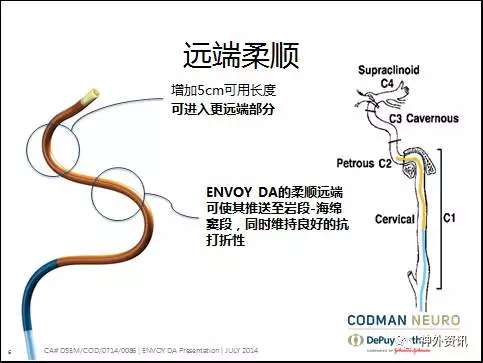

众所周知,传统的Envoy支撑性好,到位较低,满足大部分颅内血管的临床需要,对于血管严重迂曲和复杂动脉瘤的治疗需要导管提供更高的支撑力和更好地顺应性,所以有着更柔软头端,比普通导引导管上的更远的远端通路导引导管更能满足临床需求。

ENVOY® DA 远端通路导引导管在介入手术中可以突破颈内动脉岩谷段到达更远端甚至更下一级血管,在一些复杂颅内动脉瘤、终末支血管供血的AVM以及病变近端通路迂曲的情况下为微导管及支架导管提供了稳定的支撑力,为介入手术的成功提供了保障。

1. Envoy DA远端通路导引导管,是强生公司在Envoy导引导管的基础上研发的产品,在保留Envoy近端支撑力的同时,柔软的8cm柔软段能很好的锚定在迂曲的颅内血管中。对于绝大部分的神经介入复杂治疗不需要使用长鞘,为手术提供了便利。

2. 病变血管迂曲的复杂动脉瘤、终末支血管供血的AVM一直是神经介入手术的治疗难点,远端通路导引导管Envoy DA能够为微导管提供更好的稳定性和支撑力,为这类手术的成功治疗提供了保障。